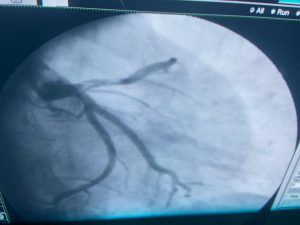

ومن جانبه أوضح الدكتور شرف الدين شاذلي رئيس وحدة قسطرة القلب بالمستشفى الجامعي، أن فريق العمل بجراحة الأوعية الدموية قام بعمل سحب وإذابة جلطة الساق، وبعدها تدخل أطباء وحدة القسطرة لعمل قسطرة عاجلة للقلب لسحب الجلطة وتركيب دعامة الشريان التاجي عن طريق الذراع، وبفضل الله وعنايته، المريض الآن بحالة جيدة ويتماثل حالياً للشفاء في عناية القلب بالمستشفى الجامعي.